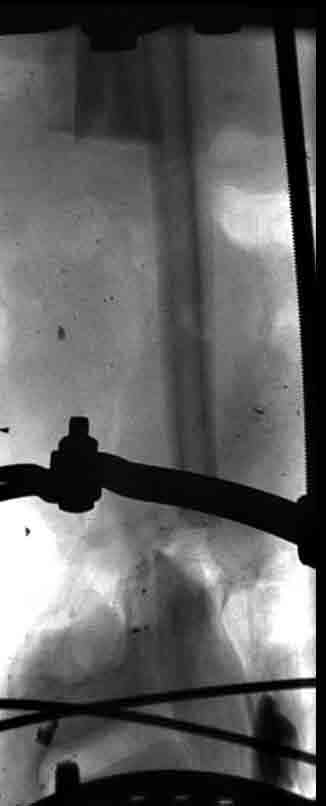

5. Ну и чтобы не быть голословным. Молодой человек подорвался на фугасе (Чечня, 2005 год). Свежие рентгенограммы:

Соответственно ожоги и дефект мягких тканей, переломы костей стопы и пр. Наложили аппарат

Илизарова (как придется), хирургически обработали и героически заживляли мягкие ткани с многочисленными кожными пластиками. В итоге через полгода я принял его вот таким: